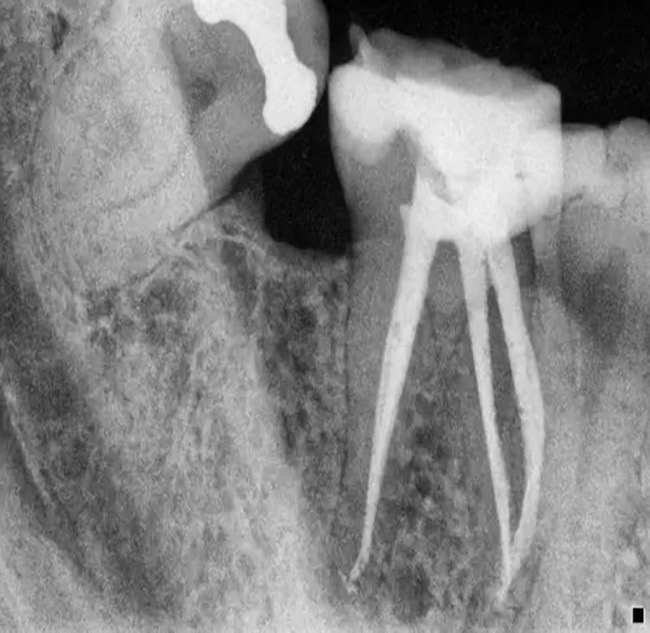

Root Canal Treatment

3. Beneath the layers of dental and dentine enamel is the dental pulp – the pulp is a soft tissue that contains the nutrients and nerves, creating feelings of hot and cold. The pulp is located in the root canal of the tooth and the tooth may contain single or multiple canals.

Root canal treatment becomes necessary when the dental pulp is infected. The cause of the damage can be due to:

• Diagnosis: The dentist assesses the tooth’s condition through X-rays and recommends a root canal if the pulp is infected or inflamed.